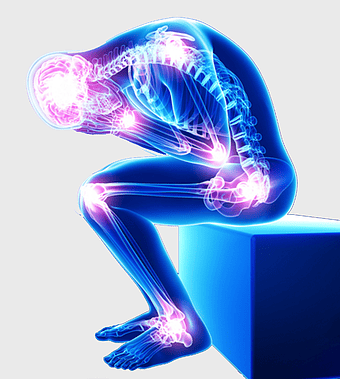

knee pain illustration, osteoarthritis joint pain, medical pain management, violet medical, skeletal joint health, chronic pain therapy, human anatomy injury -

rheumatoid arthritis illustration, chronic pain therapy, joint replacement surgery, blue violet human skeleton, skeletal anatomy diagram, arthritis pain relief methods, orthopedic health visual aids -

arthritis pain symptoms, rheumatoid arthritis illustration, joint pain areas, human body anatomy, skeletal health issues, medical visualization, chronic joint discomfort -